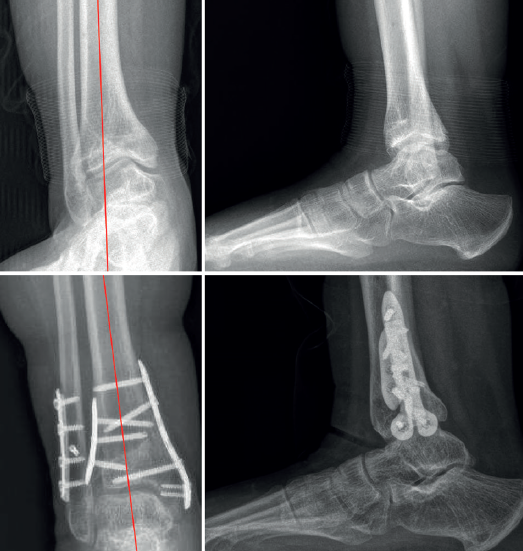

mact.1501.fs2301010-figura2.png

Figura 2. A: deformidad en varo postraumática congruente con osteotomía tibial medial y del peroné con 2 agujas en el punto de bisagra que actúan como freno de la sierra o los escoplos y evitan la traslación en el momento de apertura medial; B: apertura medial progresiva con pinzas. Nótese la simulación del eje tibial con cable de bisturí eléctrico.

- Osteotomía de apertura medial (Tabla 4): el plano de la osteotomía de apertura se marca con una aguja de Kirschner colocada a 5 cm desde la cortical medial de la punta del maléolo. Idealmente, la aguja debe ser dirigida al tercio superior de la sindesmosis de forma oblicua para evitar la rotura de la cortical lateral cuando esta funcione de bisagra. Si existe aumento de la inclinación del astrágalo (talar tilt > 4°), se ha demostrado en un reciente estudio que una mayor oblicuidad de la osteotomía hacia la parte más distal de la sindesmosis (1 cm proximal de la línea articular) puede corregir mejor la inclinación talar sin alterar el eje mecánico de carga(16). Para evitar el paso de la sierra a la cortical lateral, se puede colocar una aguja de freno en la parte lateral que, además, previene una inesperada fractura en la zona de bisagra al hacer la apertura medial (Figura 2). La cuña de adición necesaria para la corrección deseada puede ser planificada según una fórmula matemática (y = x tang α), (Figura 3)(17) sobre la TC preoperatoria, sobre todo para los casos donde se planee una sobrecorrección biplanar (planos coronal y sagital). Además, la corrección sostenida con pinzas de láminas distractoras puede comprobarse en fluoroscopia intraoperatoria mediante la simulación de un eje mecánico de la tibia con el cable del bisturí eléctrico (Figura 2).